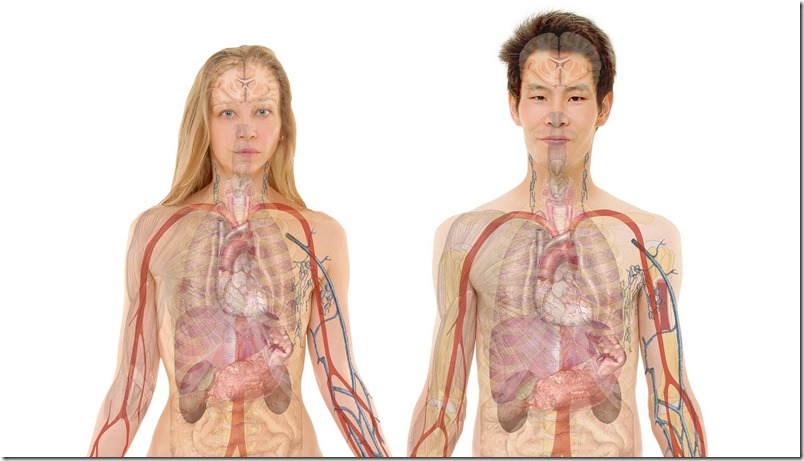

El hígado es el órgano interno más grande y la glándula más grande del cuerpo humano. El hígado juega un papel vital en muchas funciones corporales que van desde la producción de proteínas a través de la coagulación de la sangre y también regula los niveles de colesterol, glucosa y el metabolismo de hierro. Y filtrando continuamente nuestra sangre, el hígado desintoxica y limpia nuestros cuerpos. A excepción del cerebro el hígado es el órgano más complejo, por lo que mantenerlo en buen estado de salud es imperativo. Un punto único y muy positivo es que nuestro hígado es realmente capaz de repararse a sí mismo, lo que significa que, dependiendo de la causa del daño y si es detectada a tiempo, pueden de hecho hacer recuperaciones completas.

“Las miles de sistemas de enzimas que son responsables de prácticamente todas las actividades del cuerpo se construyen en el hígado”, escribe el Dr.Karl Maret, MD, de la importancia de la función dinámica hepática. “El buen funcionamiento de los ojos, el corazón, el cerebro, las gónadas, las articulaciones y los riñones, todos dependen de una buena actividad del hígado y por ello la importancia de limpiar el hígado naturalmente”.